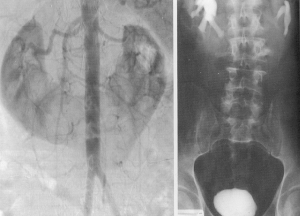

Arteriografia renala este examenul uzual radiologic în evidentierea stenozelor arteriale. Se observa micsorarea calibrului arterei renale, eventual si dilatarea poststenotica. Stenoza poate fi situata pe oricare portiune a arterei. În timpul nefrografic se vede un rinichi mic, cu contur regulat (când ischemia e totala) sau cu boseluri si ancose, în caz de ischemie partiala sau infarct renal. În cayuri selectate, se poate face dilatare percutana a arterei cu sonda cu balonas.

La urografia i.v., rinichiul ischemic se prezinta prin: întârzierea unilaterala a excretiei, diminuarea secretiei substantei de contrast sau rinichi mut, nesecretant, dar cu aspect morfologic normal al sistemului pielo-calicial la pielografia ascendenta; scaderea cu peste 1 cm în toate diametrele a rinichiului ischemic; contur neregulat, cu ancose în dreptul infarctului renal.